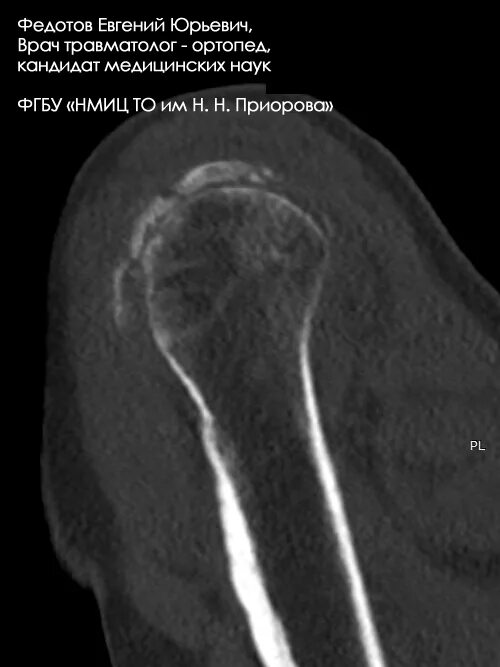

Перелом б бугорка